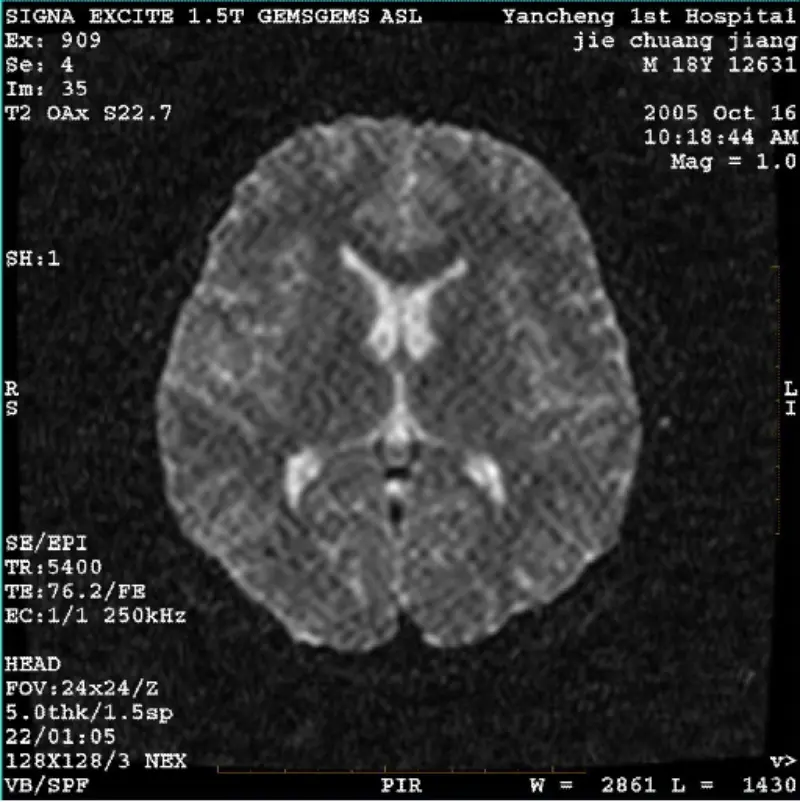

Прочетете ощеСИСТЕМА: 1.5T Signa Twin Excite II (Версия на софтуера 11.0M4) ПРОБЛЕМ/СИМПТО DWI (режим на мащабиране и цял режим) и fiesta (режим на мащабиране и цял режим) има изображение видим мрежест или кадифеен артефакт, независимо при използване на бобина или глава намотка, друго рутинно изображение ......